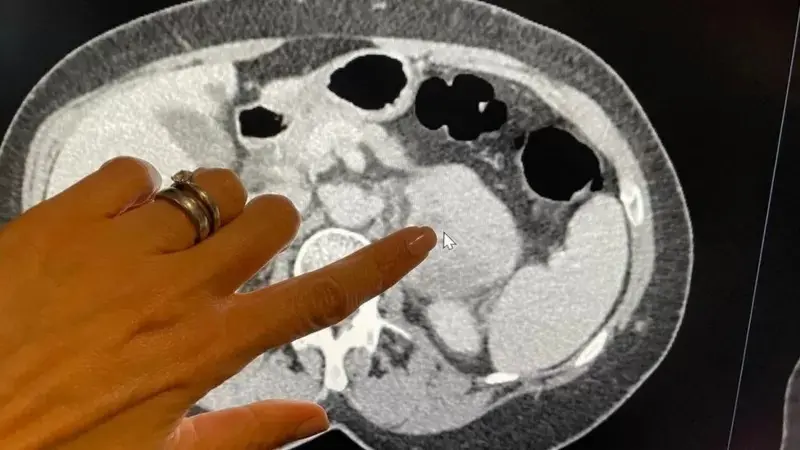

محققان در نشریه لنست انکولوژی نوشته‌اند که در اسکن ۱۷۰ بیمار از تکنیکی به نام رادیومیک برای شناسایی علائم غیرقابل مشاهده «سارکوم خلفی صفاقی» که در بافت هم‌بند پشت شکم ایجاد می‌شود، استفاده کرده‌اند.

با این داده‌ها، الگوریتم هوش مصنوعی توانست تهاجمی بودن ۸۹ تومور دیگر بیماران در بیمارستان‌های اروپا و آمریکا را از طریق اسکن، بسیار دقیق‌تر از نمونه برداری که در آن تنها بخش کوچکی از بافت سرطانی زیر میکروسکوپ تجزیه و تحلیل می شود، درجه بندی کند.

وقتی تینا مک لاگلان، پرستار دندانپزشکی، در ژوئن سال گذشته، پس از درد معده با سارکوم در پشت شکمش تشخیص داده شد، پزشکان برای یافتن این مشکل به تصاویر اسکن توموگرافی کامپیوتری (CT) تکیه کردند.